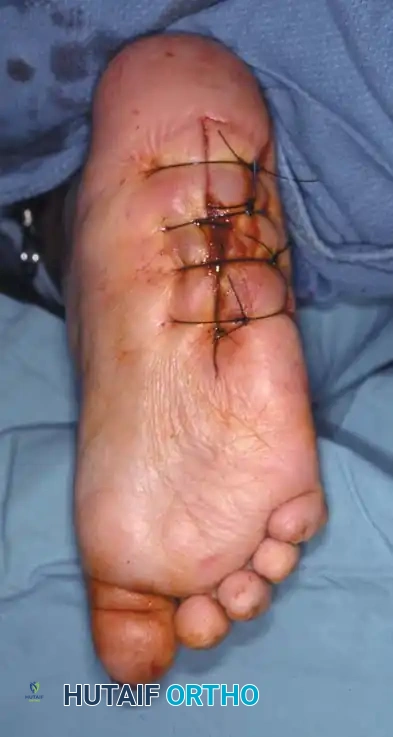

If an ulcer is driven purely by a localized bony prominence in an otherwise stable foot (Eichenholz Stage III), a simple exostectomy may suffice. The most common site is the plantar-medial aspect of the midfoot (prominent medial cuneiform or base of the first metatarsal). Care must be taken to resect enough bone to relieve pressure without violating the remaining stabilizing ligaments, which could trigger a secondary collapse.

Arthrodesis and Realignment

When deformity correction is required, formal arthrodesis is performed. The goal is to create a plantigrade, stable, and braceable foot.